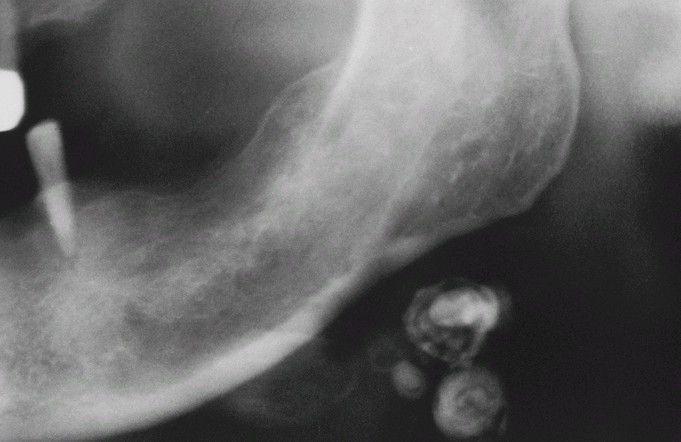

Tuberculosis (TB).

Multiple calcified cervical lymph nodes.